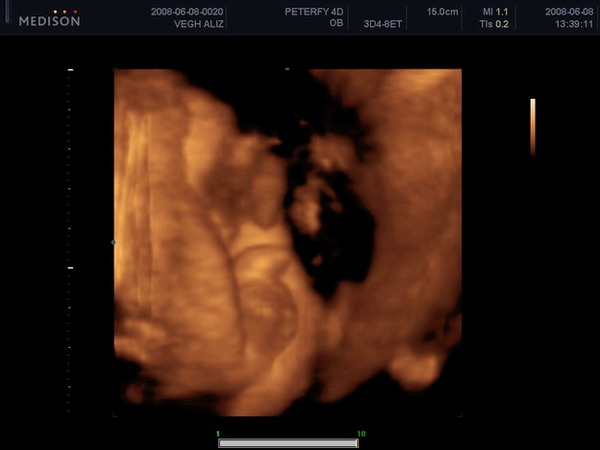

Roni, nagyon jó a 4D-s kép.

Le sem tagadhatná, hogy kisfiú.